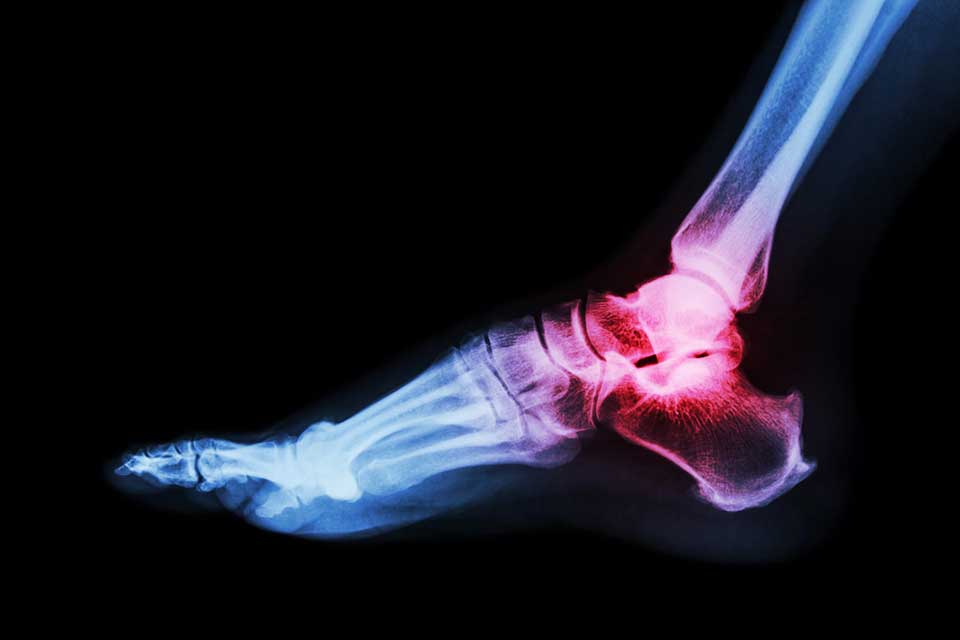

Gout is a common form of inflammatory arthritis, which affects 2.4% of adults in the UK. The painful condition is caused by high levels of uric acid in the blood which develops needle-like crystals in the joint.